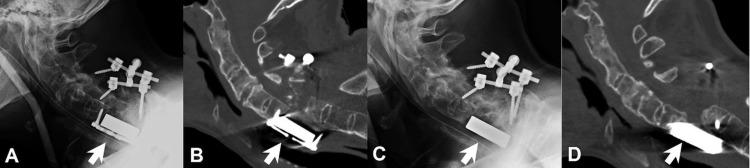

Although cage subsidence and dislodgement are not uncommon in anterior cervical spine surgery, missing cages have seldom been reported. This is the first report of the disappearance of a metallic corpectomy cage after anterior cervical fusion. A 63-year-old man, who had a history of ankylosing spondylitis and diabetes mellitus, was involved in a motor vehicle accident that broke his neck. The traumatic C6 burst fracture caused myelopathy and instability, which required surgery. He then underwent anterior C6 corpectomy with circumferential fixation, including anterior plating and posterior lateral mass screws from C5-C7. There was a significant improvement in neurological function after the surgery and he could ambulate independently. However, upon a visit at six months postoperation, there was dislodgement of the anterior cervical plate and cage. An attempt to revise the anterior fusion construct was made subsequently, but this surgery could only remove the plate. The metallic cage was left in place during the revision surgery because it was firmly incorporated into the C5 and C7 vertebra and could hardly be adjusted intraoperatively. There were no other interventions during the interval. Upon his visit at 23 months after the initial surgery, the metallic cage was missing. No examinations could locate the cage anywhere in the body, including 36-inch radiographs that demonstrated completely the disappearance of the metallic corpectomy cage. The posterior arthrodesis seemed stable and the patient had no dysphagia or any other gastrointestinal symptoms. The process of the disappearance of the corpectomy cage was never noticed by the patient and he remains free of symptoms to date. The complete dislodgement of a cervical corpectomy cage that was placed anteriorly could happen without symptoms. The cage might have been expelled during bowel movements and caused little problem. Failure to achieve arthrodesis in anterior cervical fusion, therefore, must be closely monitored.

尽管颈椎前路手术中椎间融合器下沉和移位并不少见,但椎间融合器缺失的情况鲜有报道。本文首次报告了颈椎前路融合术后金属椎体切除椎间融合器消失的病例。一名63岁男性,有强直性脊柱炎和糖尿病病史,因机动车事故导致颈部骨折。创伤性C6爆裂骨折引起脊髓病和不稳定,需要手术治疗。随后他接受了C6椎体次全切除并环形固定,包括前路钢板固定和C5 - C7的后路侧块螺钉固定。术后神经功能有显著改善,他能够独立行走。然而,术后6个月复诊时,发现颈椎前路钢板和椎间融合器移位。随后尝试对前路融合结构进行翻修,但该手术只能取出钢板。翻修手术时金属椎间融合器留在原位,因为它已牢固地融合到C5和C7椎体中,术中几乎无法调整。在此期间没有进行其他干预。初次手术后23个月复诊时,金属椎间融合器不见了。包括能完整显示金属椎体切除椎间融合器消失的36英寸X线片在内的任何检查都未在体内找到该椎间融合器。后路融合似乎稳定,患者没有吞咽困难或任何其他胃肠道症状。患者从未注意到椎体切除椎间融合器消失的过程,至今仍无症状。前路放置的颈椎椎体切除椎间融合器完全移位可能没有症状。椎间融合器可能在排便时被排出,几乎没有造成问题。因此,颈椎前路融合术中未能实现融合必须密切监测。